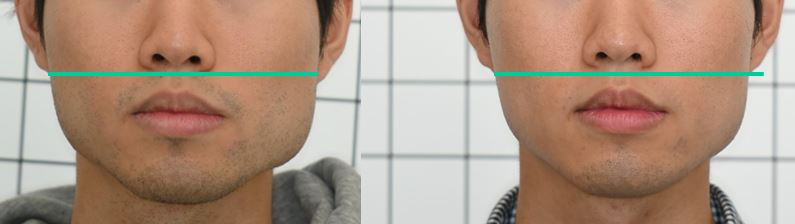

Comparison between MCB-concept Invisalign and conventional Invisalign at other dental clinics .

9월 27, 2025Does this look like ordinary orthodontic treatment to you?

When the three-dimensional position of the mandible is aligned with the facial midline and the teeth are arranged accordingly, the following changes occur.